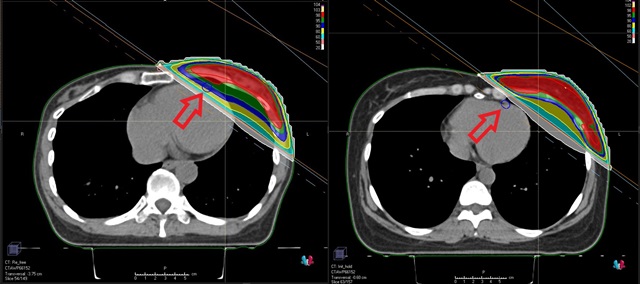

최근엔 왼쪽 유방 방사선치료 때 심장에 들어가는 방사선량을 최소화하기 위해 브레스홀딩(Breath Holding) 방사선치료가 시행된다. 방사선치료를 받는 환자에게 들숨 상태를 유지하게 하면서 치료를 진행하는 것이다. 숨을 들이마시면 폐가 부풀고 횡경막이 내려가면서 방사선 조사 부위가 심장과 멀어진다. 실제 방사선이 조사되는 시간은 30~40초 정도인데 10초씩 끊는 방식으로 진행하면 환자에게도 쉽다.

방사선을 정확히 조사하기 위한 모의치료 등도 적극 활용된다. 환자가 숨을 들이마시고 참은 상태에서 CT를 촬영하면 이에 맞춰서 방사선 조사 방향, 각도 등을 설계할 수 있다. 환자 체표면의 움직임까지 실시간으로 파악할 수 있는데 사전 CT촬영 결과가 환자의 체표면과 오차가 생길 경우 치료가 중단되는 기능도 있다.